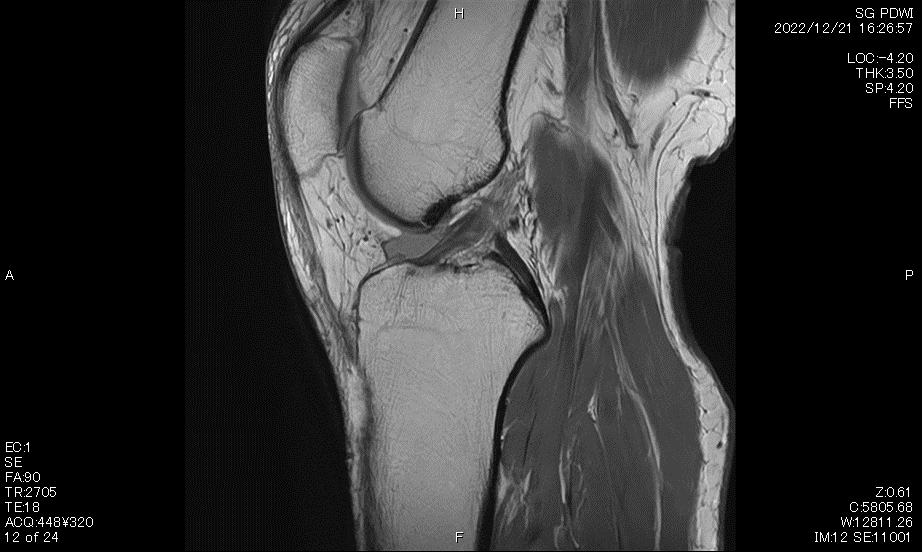

MRI検査

MRI (磁気共鳴画像) 装置は、強い磁場を形成する装置で人体に特殊な電磁波を当てて撮影を行っています。また、放射線による被ばくはありません。

当院では、Canon製 Vantage Galan 3.0TとCanon製Vantage Titan 1.5T の2台で検査を行っています。磁場強度の違いや、静音設計、開口径の大きさなどの特徴があり、検査内容に合わせて医師の判断で装置を使い分け、精度の高い良好な画像を提供しています。

主に頭部、骨、軟部組織の検査を始め、肝臓ダイナミックなど幅広く検査を行っています。